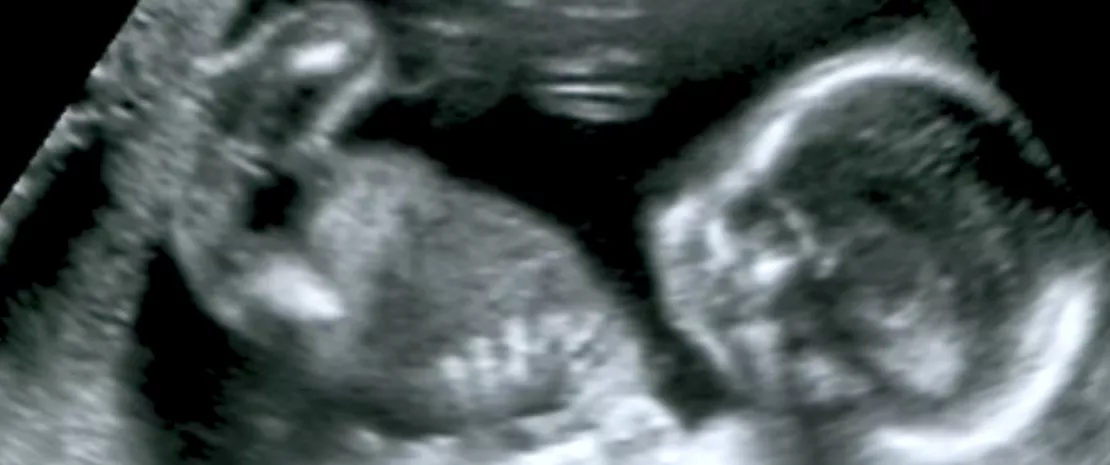

Découverte d’une communication mère-fœtus via le microbiote intestinal

Le microbiote intestinal des femmes enceintes produit des vésicules extracellulaires capables de migrer dans le liquide amniotique. Elles pourraient préparer l’intestin du fœtus à être colonisé par les microorganismes du futur microbiote.

Une équipe de chercheurs finlandais vient pour la première fois de mettre en évidence la présence, dans le liquide amniotique, de vésicules extracellulaires issues de bactéries du microbiote intestinal, chez des femmes enceintes en bonne santé 1.

Ces vésicules sont constituées de molécules bactériennes diverses (protéines, lipides, acides nucléiques…) qui pourraient jouer un rôle fondamental dans la maturation de l’intestin fœtal et l’immunité de l’enfant à naître.

Cette découverte pourrait constituer la pièce manquante pour expliquer la présence, relevée dans plusieurs études récentes, d’ADN bactérien dans le placenta, le liquide amniotique et le méconium.